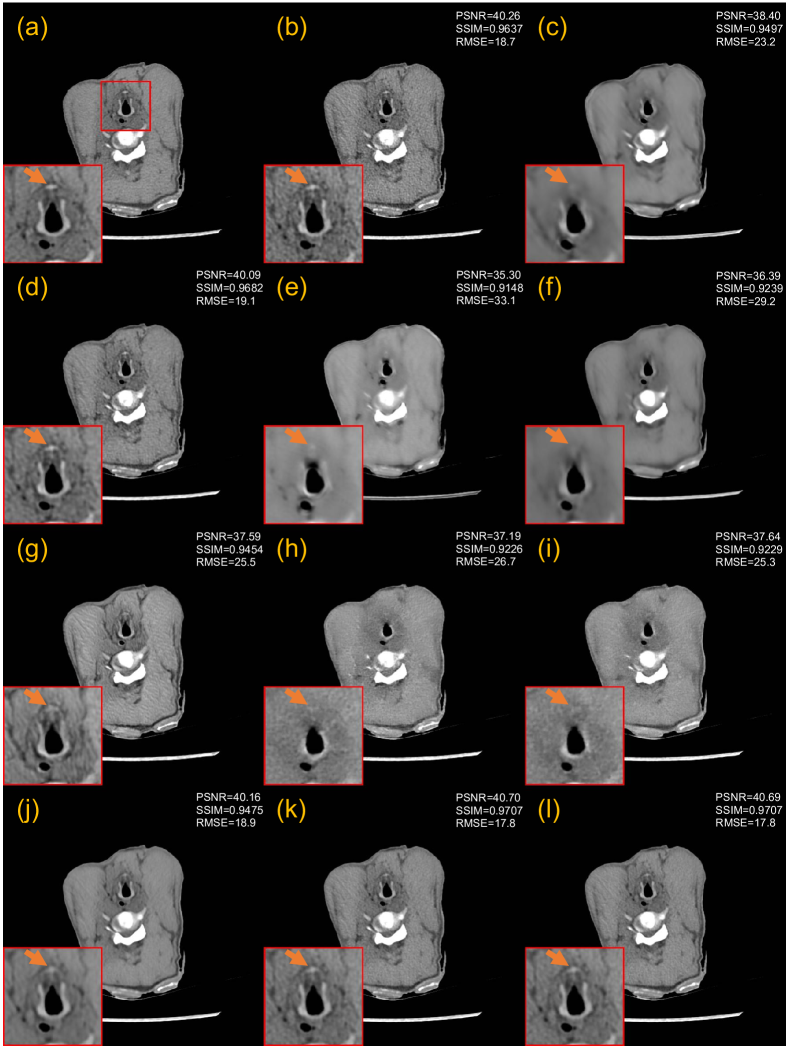

3.3.1 Evaluation on the 25% dose

Fig. 4 presents a representative slice of 25% dose test data denoised by different methods for visual comparison. The orange arrow indicates the location of the lesion in the red region of interest (ROI). Although the RED-CNN-based methods effectively remove noise from the LDCT image, it tends to blur fine details. Among the GAN-based methods, WGAN-VGG introduces velvet artifacts, and DU-GAN provides textures closer to NDCT images. CNCL-U-Net preserves the most details, but its residual map shows a noticeable difference in predicting the bone edge. Among the diffusion-based models, DDM2 exhibits obvious artifacts and CT number drift. We conjectured that this phenomenon may result from the fact that DDM2 assumes the image noise adheres to a Gaussian distribution, which deviates from the actual noise distribution of CT images. Both in terms of texture preservation and detail retention, IDDPM and our CoreDiff surpass other compared methods. For the IDDPM, lowering the number of sampling steps to 50 has little impact on the denoising performance. However, when is reduced to 10, the model produces the poorest results due to much insufficient sampling. In addition, IDDPM-1000/-50 erase the critical lesion information, while our CoreDiff retains them well. The residual map confirms that our approach has the least prediction bias.

Fig. 5 presents the qualitative results of 5% dose test data. In this ultra-low dose scenario, the FBP image suffers from significantly severe noise and streak artifacts due to the photon starvation effect, making it unacceptable for clinical diagnosis. The denoising performance of some denoising methods has a sharp decline. Fig. 5 shows that RED-CNN-based methods and CNCL-U-Net produce over-smoothed results. In addition, both PWLS and WGAN-VGG introduce noticeable artifacts to the denoised images. The DU-GAN obtains the best performance besides the diffusion-based methods. However, the denoising result of DU-GAN shrinks the lesion size. Other diffusion-based models, except for IDDPM-10 and DDM2, consistently exhibit remarkable performance in ultra-low-dose denoising tasks, showing great promise for LDCT denoising. Among them, our CoreDiff exhibits the best denoising performance both in terms of residual maps and zoomed-in ROIs. Furthermore, Fig. 6 shows the profile results of the different methods, as indicated by the blue line in the NDCT images in Fig. 5. The red arrow indicates that our CoreDiff maintains the CT number better than other methods.